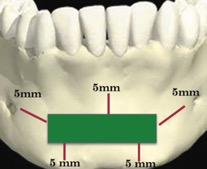

В 1992 году Misch для профилактики осложнений при получении костного блока из подбородочной области предложил правило «трёх пятёрок», при котором выделяется зона безопасности на 5 мм апикальнее от верхушек корней зубов (профилактика чувствительности зубов), на 5 мм медиальнее от ментальных отверстий (профилактика парестезии) и на 5 мм к верху от нижнего края нижней челюсти (профилактика перелома) [3] (Рис. 2).

Рисунок 2. Правило трех пятерок.jpg

Рисунок 2. «Правило трёх пятеёрок»